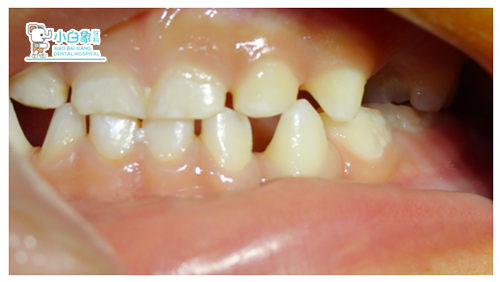

粘结后咬合像